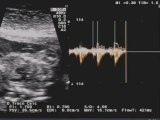

Interruzione dell'arco aortico

Ecocardiografia fetale : doppler normale